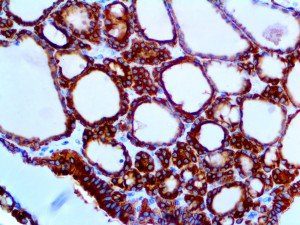

It is the ICU physician who is most likely to witness one of the deadliest manifestations of the abnormal immunological response, the cytokine storm syndrome (CSS). This response is also referred to by some as the cytokine release syndrome (CRS). CSS is characterized by continuous activation and expansion of macrophage and lymphocyte populations, which secrete large amounts of cytokines, causing the cytokine storm. This massive cytokine release is akin to hemophagocytic lymphohistiocytosis (HLH) disease, a syndrome characterized by initial unchecked and persistent activation of cytotoxic T lymphocytes and NK cells.

Clinical and laboratory manifestations of HLH include fever, enlarged liver and/or spleen, neurologic dysfunction, coagulopathy, liver dysfunction, cytopenias (i.e., low levels of erythrocytes, leukocytes, and/or platelets), hypertriglyceridemia, hyperferritinemia, hemophagocytosis, and eventually diminished NK cell activity as the immune system becomes progressively paralyzed. HLH can be familial (primary HLH) or secondary to another disease process (sHLH), such as rheumatic disease, in which it is referred to as macrophage activation syndrome (MAS, characterized by elevated ferritin).